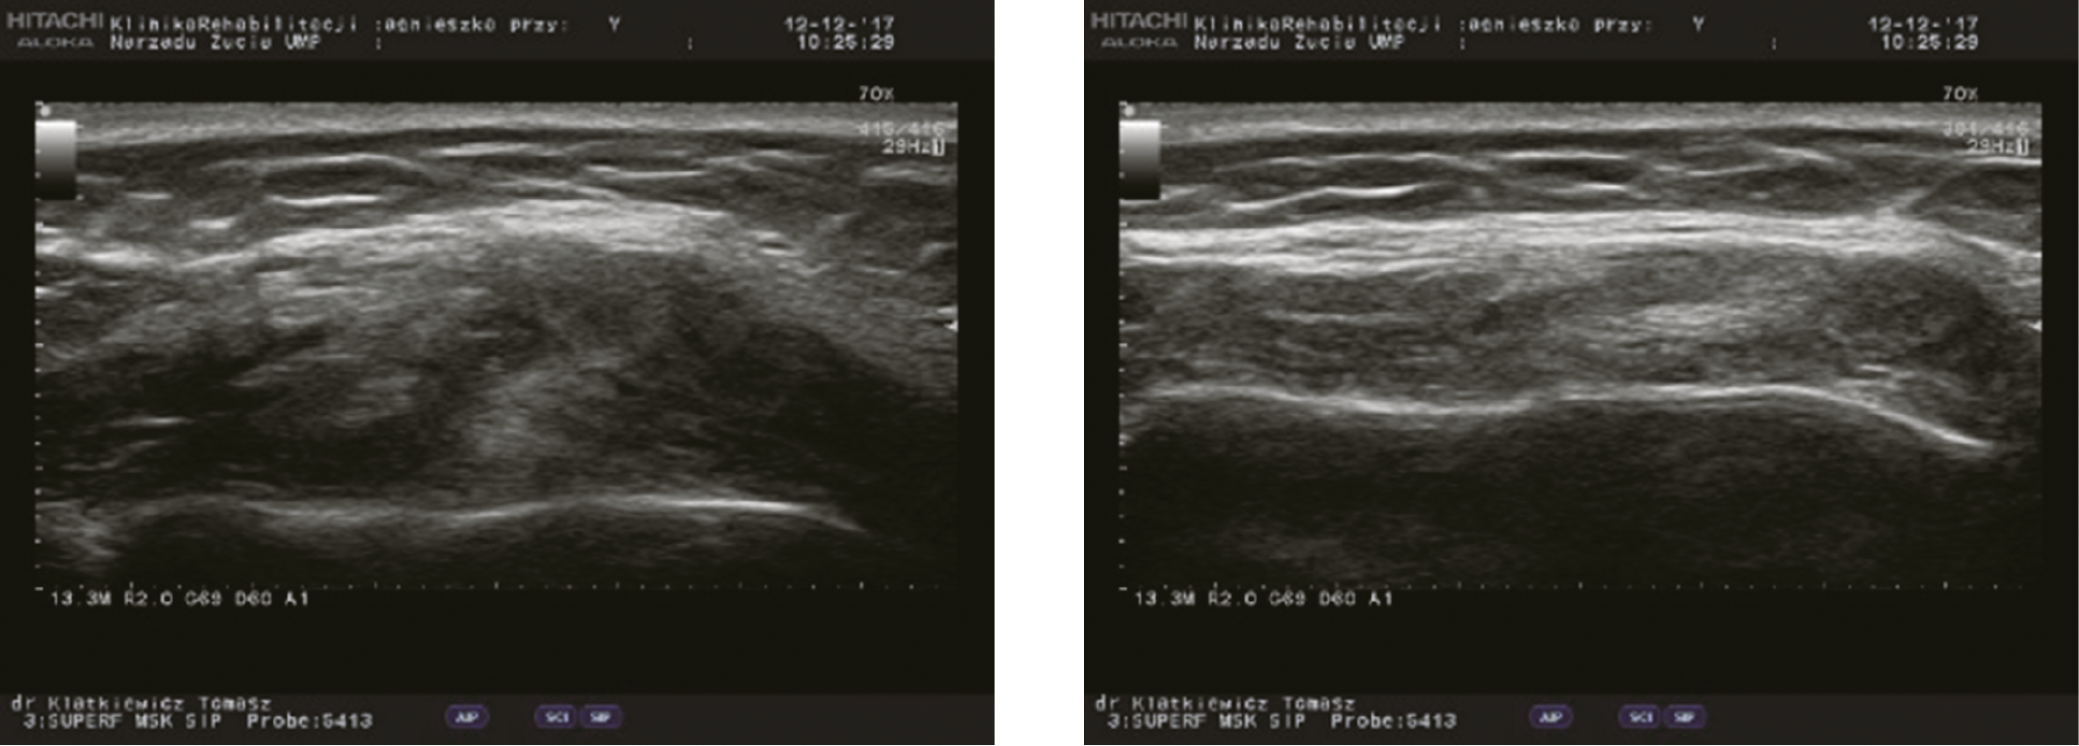

All participants were examined with the Diagnostic Criteria for Temporomandibular Disorders (DC/TMD) form.24 According to this protocol, 62 consecutive patients qualified for the study (30 men and 32 women). The average age of the patients was 25.4 years. Each individual underwent bilateral ultrasound examination of the masseter muscles. The muscles were examined with the Aloka-Hitachi F37 USG device with 12 MHz linear probe (Aloka-Hitachi, Tokyo, Japan). To achieve the most repeatable examination protocol, the muscle was virtually divided into 3 horizontal regions (lower, middle and upper) and 2 vertical regions (proximal and distal). The axial and coronal ultrasound examinations were carried out in the horizontal and vertical regions, respectively. The thickness of the masseter muscle was measured in every designated area when relaxed (muscle at rest (RMT)), with individuals resting comfortably and associated muscles in a state of minimal contractual activity, and with clenched teeth (contracted muscle (CMT)) in maximal intercuspal position (Figure 1, Figure 2, Figure 3).

The ultrasound study revealed very high (p < 0.0001) or high (p < 0.001) statistical differences between RMT and CMT in most designated areas. Only RMT measurement differences between upper and middle areas revealed no statistical difference, while the difference of proximal compared to distal region was significant at p < 0.05 (Figure 4, Figure 5, Figure 6, Figure 7).